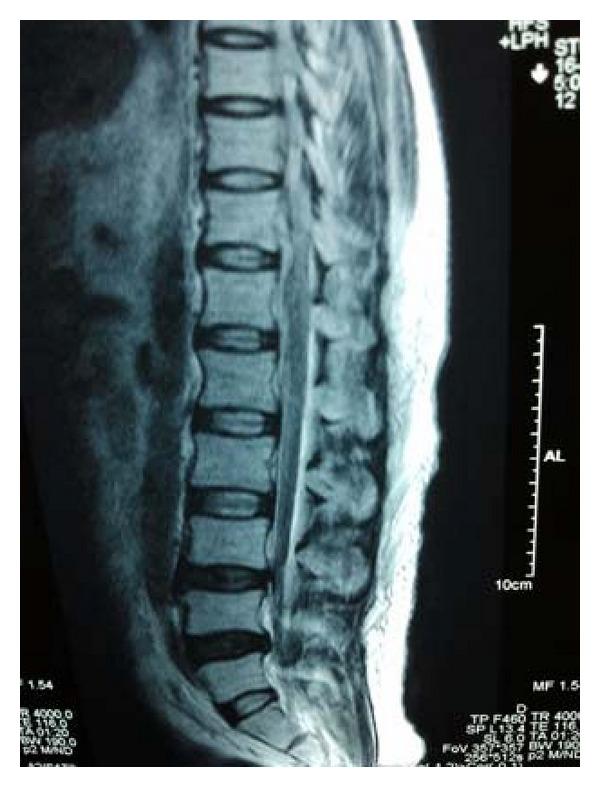

Cirrhotic or hepatic myelopathy is a rare neurological complication of chronic liver disease usually seen in adults and presents as a progressive pure motor spastic paraparesis which is usually associated with overt liver failure and a surgical or spontaneous systemic portocaval shunt. We describe the development of progressive spastic paraparesis, in a patient with alcoholic cirrhosis with portal hypertension and portal colopathy who presented with the first episode of hepatic encephalopathy. The patient had not undergone any shunt procedure.